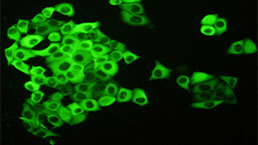

The antibody is a rabbit polyclonal antibody raised against SETBP1. It has been selected for its ability to recognize SETBP1 in immunohistochemical staining and western blotting.